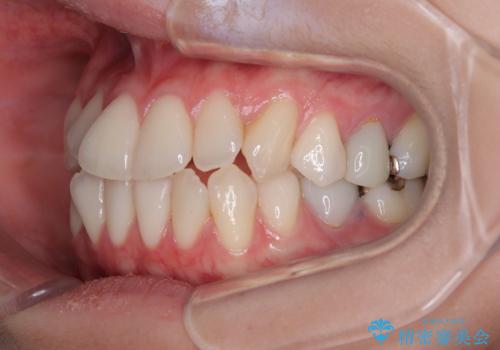

- 上下前歯のデコボコとクロスバイトを気にして来院された患者様です。

治療済みの処置歯が多いため、インビザラインを用いて矯正治療を行うこととしました。

下顎臼歯部にブリッジが装着されており、移動不可のため、IPR(歯と歯の間を削る)と歯列全体を拡大させることで、歯並びを整えていくこととしました。